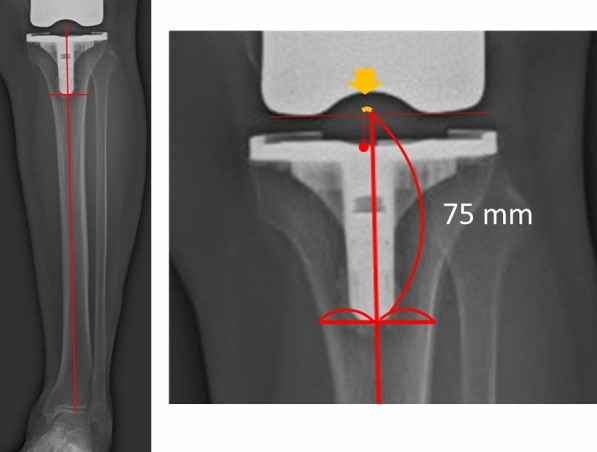

Methods: A total of 86 consecutive knees were included. The mediolateral positions of the femoral and tibial components were measured on the postoperative long-leg radiographs. The mediolateral position of the femoral and tibial components was defined relative to the femoral distal anatomical axis and the tibial mechanical axis. The lateral position of the component was denoted as positive. The lateral translation of the femoral and tibial components was defined as the distance between the preoperative femoral and tibial centers and the postoperative center of the respective component. The Knee Society Score (KSS), New Knee Society Score (2011 KSS), and the Timed Up and Go (TUG) test results were evaluated 2 years postoperatively. Spearman's correlation coefficient was calculated.